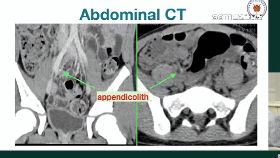

40歲女胃劇烈疼痛!醫驚:闌尾腫了7公分

胃痛絕不能忽視!禾馨民權健康管理診所院長林相宏表示,...